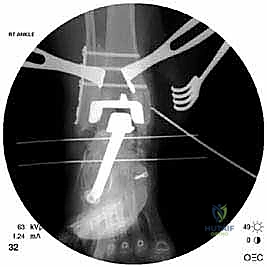

كسور الكعبين (Malleolar Fractures) المصاحبة للمفصل الصناعي

من أعقد التحديات التي تواجه جراحي العظام هي حدوث كسور في الكعب الداخلي (Medial Malleolus) أو الخارجي (Lateral Malleolus) في وجود مفصل صناعي. تحدث هذه الكسور لعدة أسباب:

علاج هذه الكسور يتطلب مهارة فائقة من الدكتور محمد هطيف، حيث يتم استخدام تقنيات الجراحة الميكروسكوبية وتثبيت الكسور باستخدام صفائح معدنية دقيقة ومسامير (Locking Plates) دون المساس بثبات المفصل الصناعي، أو يتم دمج علاج الكسر ضمن عملية مراجعة المفصل الكلية إذا كان المفصل نفسه تالفاً.

يتم إدخال المفصل الجديد المخصص للمراجعة، والذي يحتوي غالباً على سيقان (Stems) تدخل عميقاً في عظمة الساق وعظمة الكاحل لضمان الثبات الميكانيكي. في حال وجود كسور في الكعب، يتم تثبيتها في هذه المرحلة.

يتم خياطة الأربطة والأنسجة الرخوة والجلد بطرق تجميلية دقيقة لتقليل الندبات وسرعة الالتئام، ثم توضع القدم في جبيرة خلفية واقية.